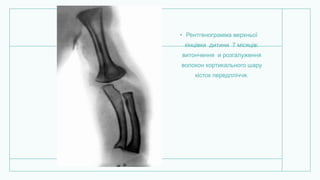

• Рентгенограмма верхньої

кінцівки дитини 7 місяців:

витончення и розгалуження

волокон кортикального шару

кісток передпліччя.

• Рентгенограмма верхньої кінцівкидитини 7 місяців: витончення и розгалуження волокон кортикального шару кісток передпліччя.